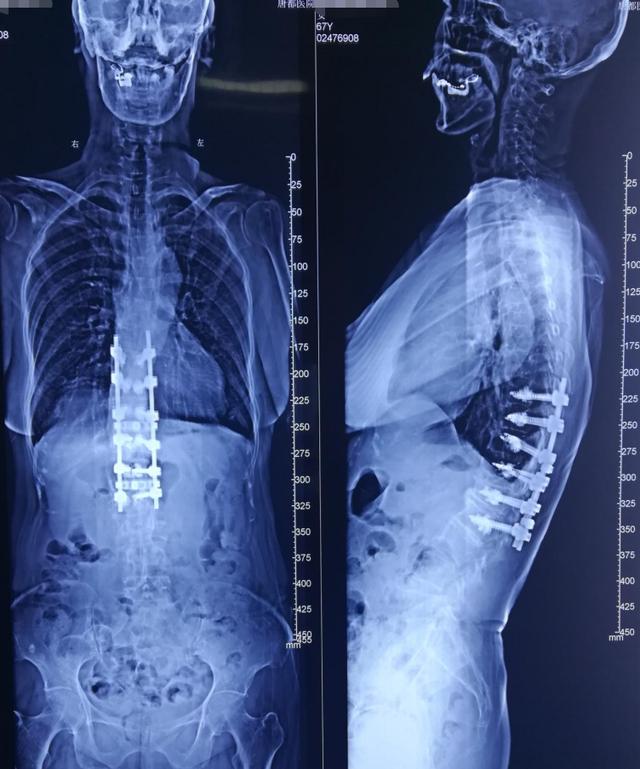

病例分享胸腰段脊柱后凸畸形

图片尺寸640x769

后路手术矫形治疗青少年特发性脊柱侧凸畸形(附图片

图片尺寸1704x2272